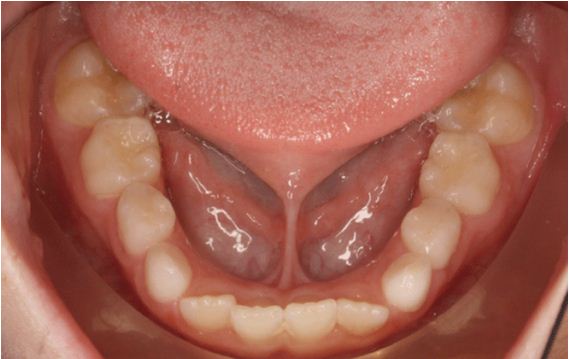

Thắng lưỡi

Thắng lưỡi ngắn

Bình thường lưỡi có thể đưa ra phía trước và hai bên, đầu lưỡi có thể đưa lên vòm miệng. Tuy nhiên, khi lưỡi bị hạn chế vận động, đầu lưỡi không thể đưa lên vòm miệng thì được gọi là dính thắng lưỡi hay thắng lưỡi ngắn. Đây là một dị tật bẩm sinh mà bất kì ai cũng có thể mắc phải. Dấu hiệu nhận biết:

- Khó bú hoặc khi bú phát ra âm thanh ở trẻ sơ sinh.

- Đầu lưỡi hình trái tim khi đưa lưỡi ra phía trước.

- Phát âm không chuẩn.

- Có thể bị xoay các răng cửa giữa hàm dưới.